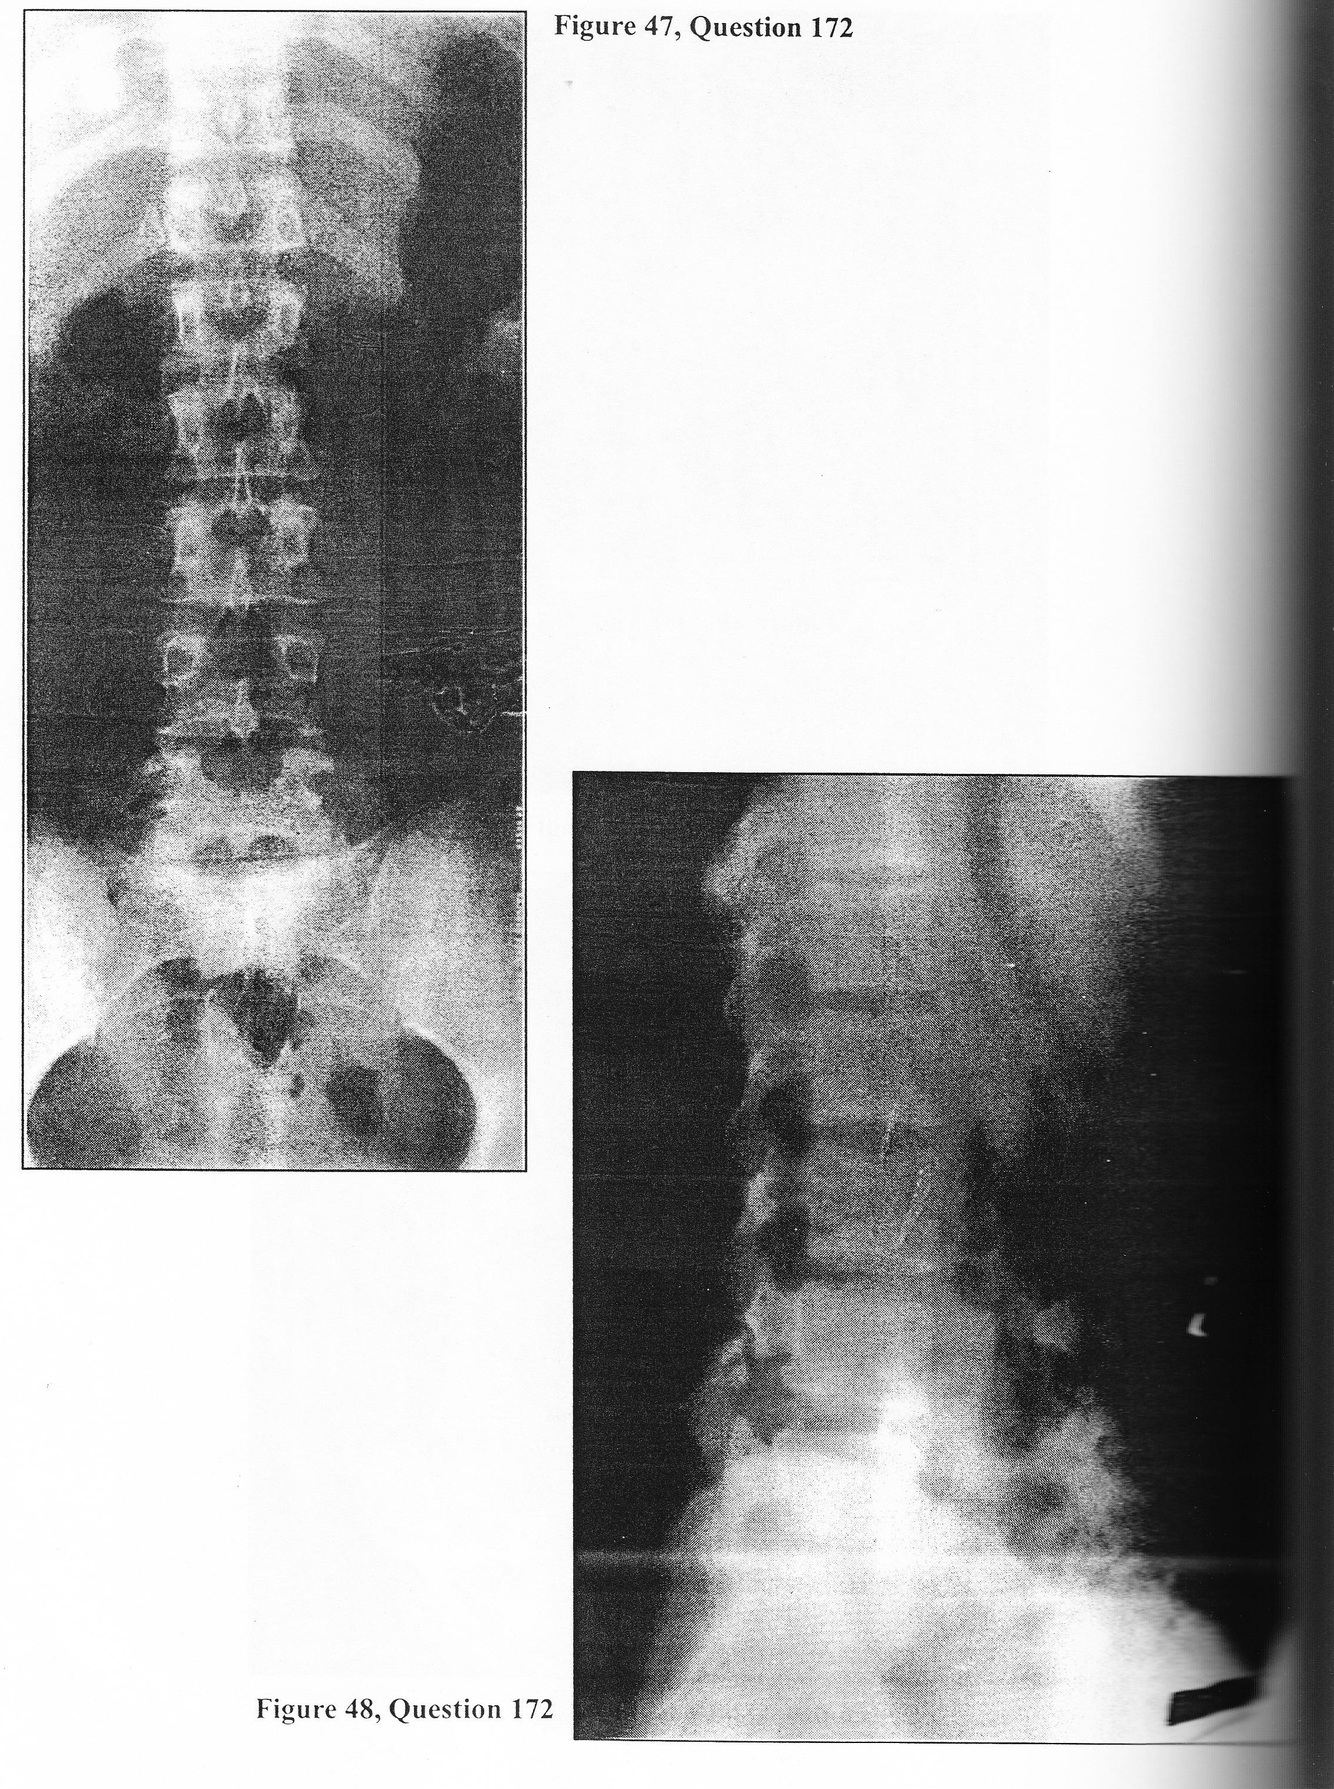

A 26-year-old male presents complaining of a two-year history of gradually progressive low back pain. It has been intermittent in nature, aggravated by physical activity, and relieved by rest. His most recent exacerbation occurred one month ago during a triathalon. The pain remains localized to the low back region with radiation into both buttocks but not the legs. He can no longer participate in his usual sports because of discomfort. Physical examination reveals the young man to be neurologically intact. Straight- leg raising and femoral stretch testing are normal. There is no clinical evidence of kyphoscoliosis. There is no joint tenderness. Range of motion of the lumbar region is normal. Plain x-rays accompany the patient (Figures 47 and 48). 172. At this point you WOULD:

A. prescribe anti-inflammatory and analgesic medications, reduced activity, and external bracing

A 26-year-old male presents complaining of a two-year history of gradually progressive low back pain. It has been intermittent in nature, aggravated by physical activity, and relieved by rest. His most recent exacerbation occurred one month ago during a triathalon. The pain remains localized to the low back region with radiation into both buttocks but not the legs. He can no longer participate in his usual sports because of discomfort. Physical examination reveals the young man to be neurologically intact. Straight- leg raising and femoral stretch testing are normal. There is no clinical evidence of kyphoscoliosis. There is no joint tenderness. Range of motion of the lumbar region is normal. Plain x-rays accompany the patient (Figures 47 and 48).

A. flexion and extension lateral lumbar radiographs